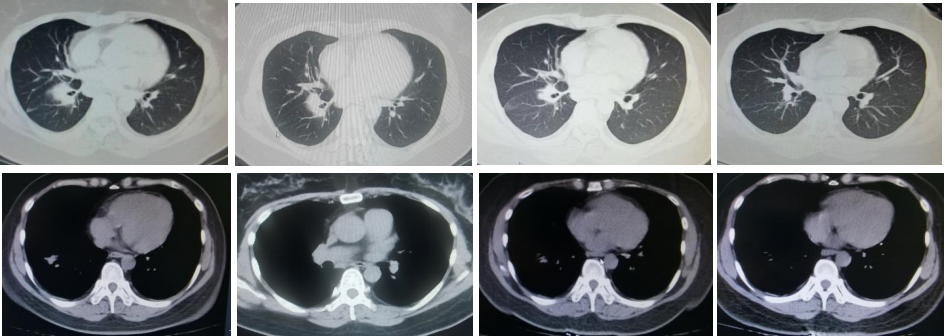

第二阶段:2024年5月29日,胸部CT示右肺下叶团片灶,较前减小。由于患者在使用双膦酸盐后出现严重的发热及骨痛等不良反应,遂将骨保护治疗方案调整为地舒单抗注射液。

第三阶段:2024年9月20日,胸部CT示右肺下叶团片灶、纵隔及右肺门肿大淋巴结,结合病史考虑肺癌并淋巴结转移性肿大,较前片(2024年5月29日)减小。后续治疗方案调整为“PD-1抑制剂单药维持治疗+地舒单抗抗骨转移治疗”。

2025年7月16日:胸部CT示右肺下病灶较前减小。

2. 最初的抗骨转移治疗出现严重的不良反应后,患者的骨保护治疗调整为地舒单抗,目前颈椎及下肢疼痛症状控制,无胸腰椎疼痛症状,日常工作完全不受影响,ECT复查显示骨核素浓聚影明显变淡;

3. 抗肿瘤免疫治疗维持阶段同步联合地舒单抗治疗,局部骨转实现了良好控制,还大幅缩小了肺部及肝脏的转移灶,达到了联合用药协同增效的治疗效果,患者整体病情得到有效控制。